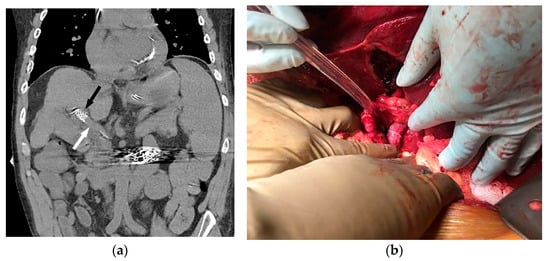

Figure 3.

Coronal non-contrast CT (a) performed two days later (same patient as Figure 1 and Figure 2) demonstrates a larger-caliber portal vein (white arrow). The caudal aspect of the TIPS is noted (black arrow). The patient underwent successful orthotopic liver transplant approximately 1 year later (b), and remains well after 53 months of follow-up.